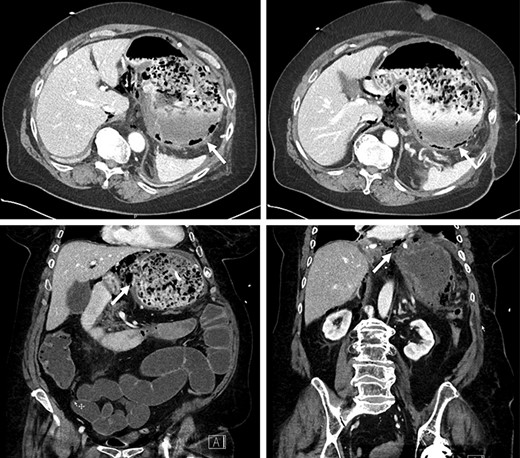

Due to inadequate oral intake and weight loss, an upper gastrointestinal endoscopy was performed 1 year later. An anastomotic stricture was objectified, for which a stent was installed (Fig. 3). The stent was removed 6 weeks later, and the width of the anastomosis was appropriate (Fig. 4).

Esophagojejunal anastomosis after removal of the endoscopic stent.